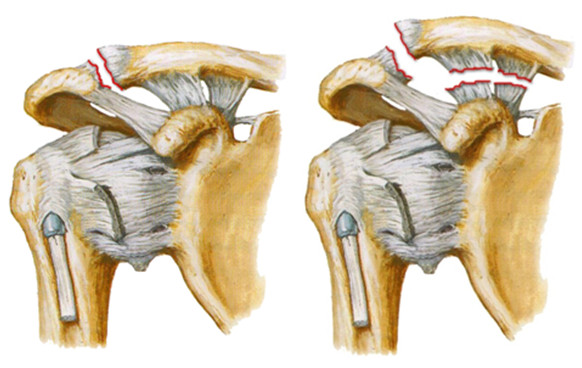

Соединения, которые образуют суставные концы ключицы, являются крепкими и прочными благодаря крепким связкам. В зависимости от степени нарушения их целостности может быть диагностирован подвывих (неполное смещение суставного конца ключицы) или вывих ключицы (полное смещение ее суставного конца).

- при осмотре – при вывихе со стороны ключично-акромиального сочленения акромиальный конец ключицы поднят вверх. Мягкие ткани в области вывиха опухшие;

- подвывих ключицы – частичное смещение суставного конца данной кости;